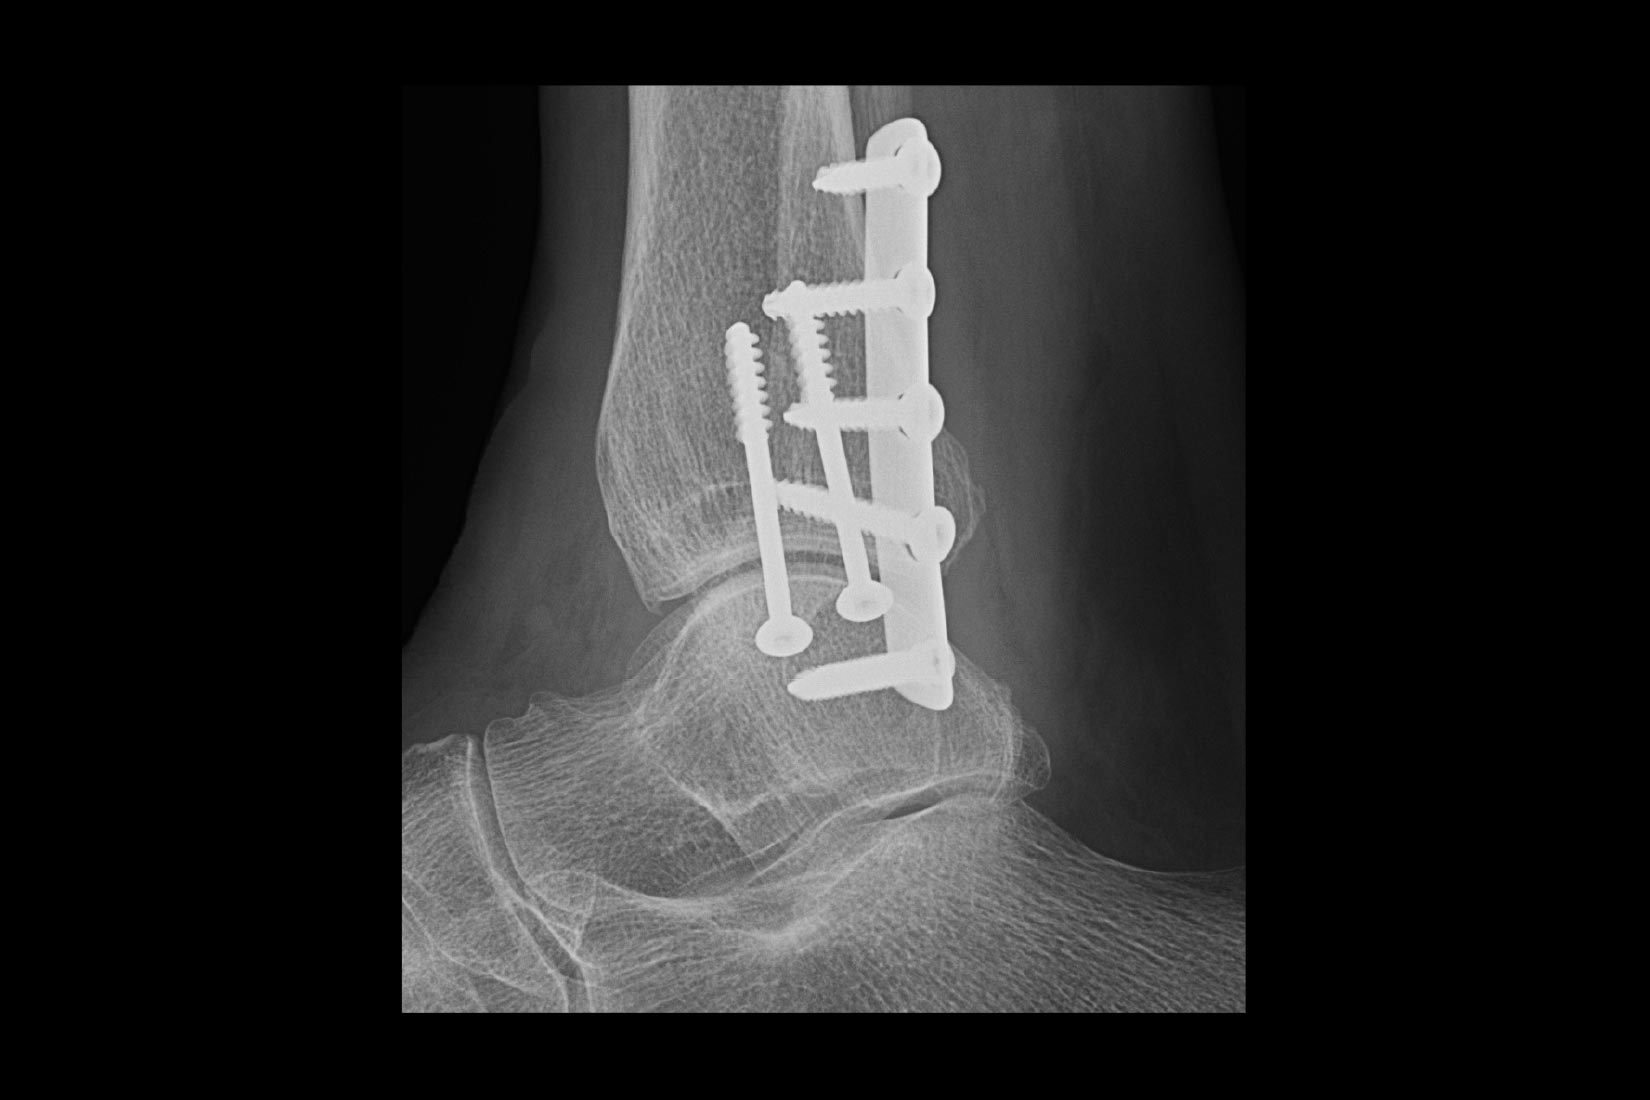

Musculoskeletal (MSK)

A curved array on one side and linear array on the other of the dual wireless probe enables clear assessment of deep and shallow anatomy without switching probes.